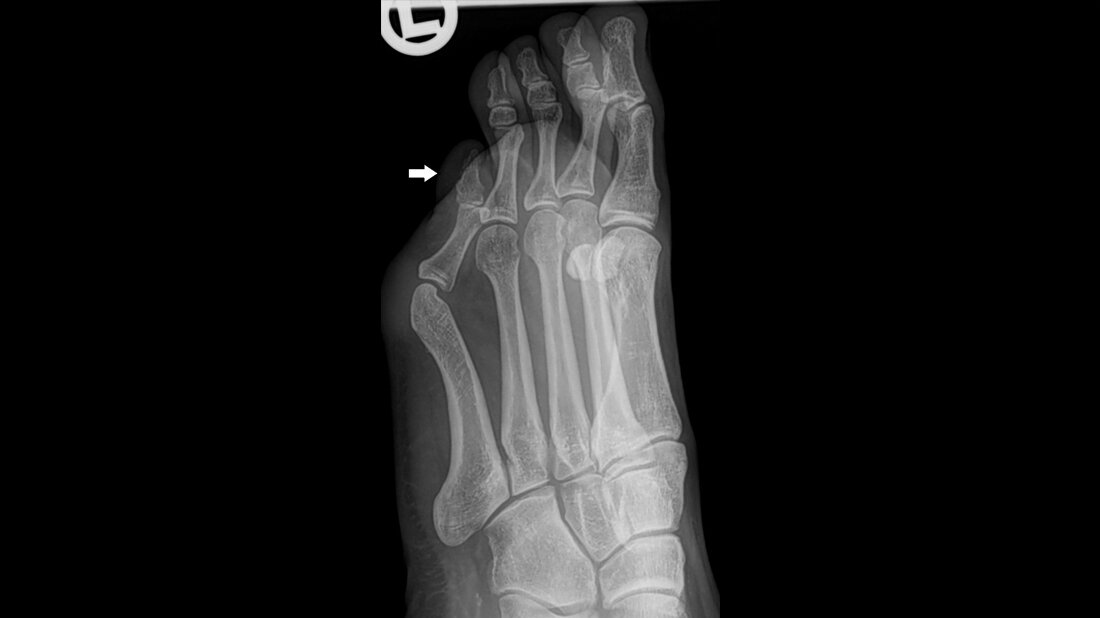

Anomalien und Normvarianten – Skelettale Veränderungen 3.42: Digitus quintus varus superductus

Das Überlappen der 5. Zehe ist meist eine kongenitale Deformität mit dorsaler Subluxation und Adduktion des 5. Metatarsophalangealgelenks. Die Fehlposition der 5. Zehe mit Überlappen der 4. Zehe ist ein Befund in der Orthopädie, der selten einer operativen Korrektur bedarf.

Overlapping fifth toe is thought to be a congenital deformity characterized by the proximal phalanx dorsally subluxating and adducting on the fifth metatarsophalangeal joint. It is a finding in orthopaedics which rarely requires operative therapy.